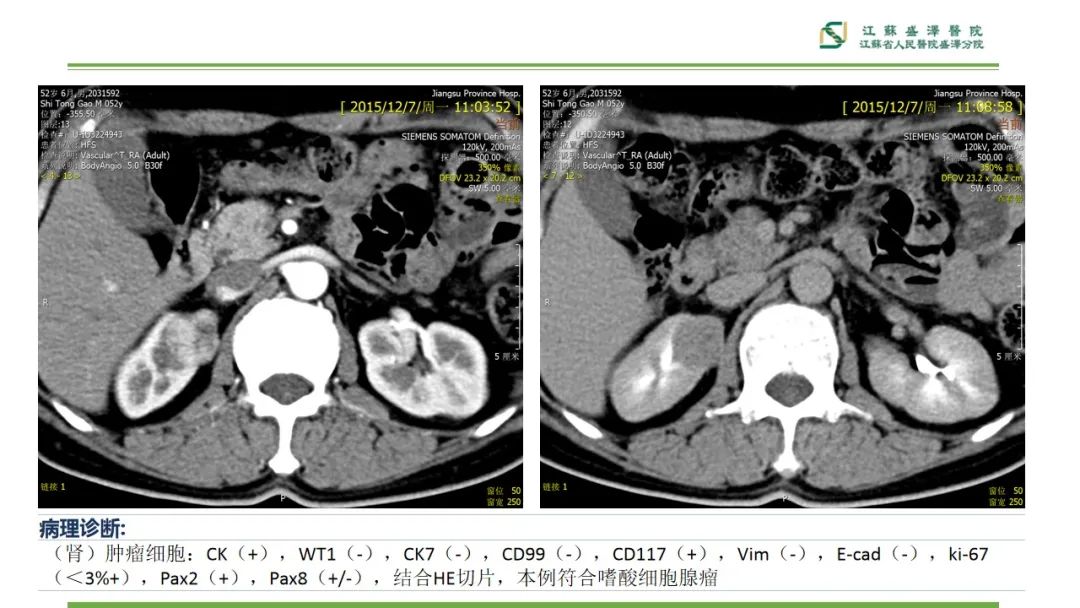

【PPT】肾脏实性肿瘤的良恶性鉴别--影像诊断思路分析-5